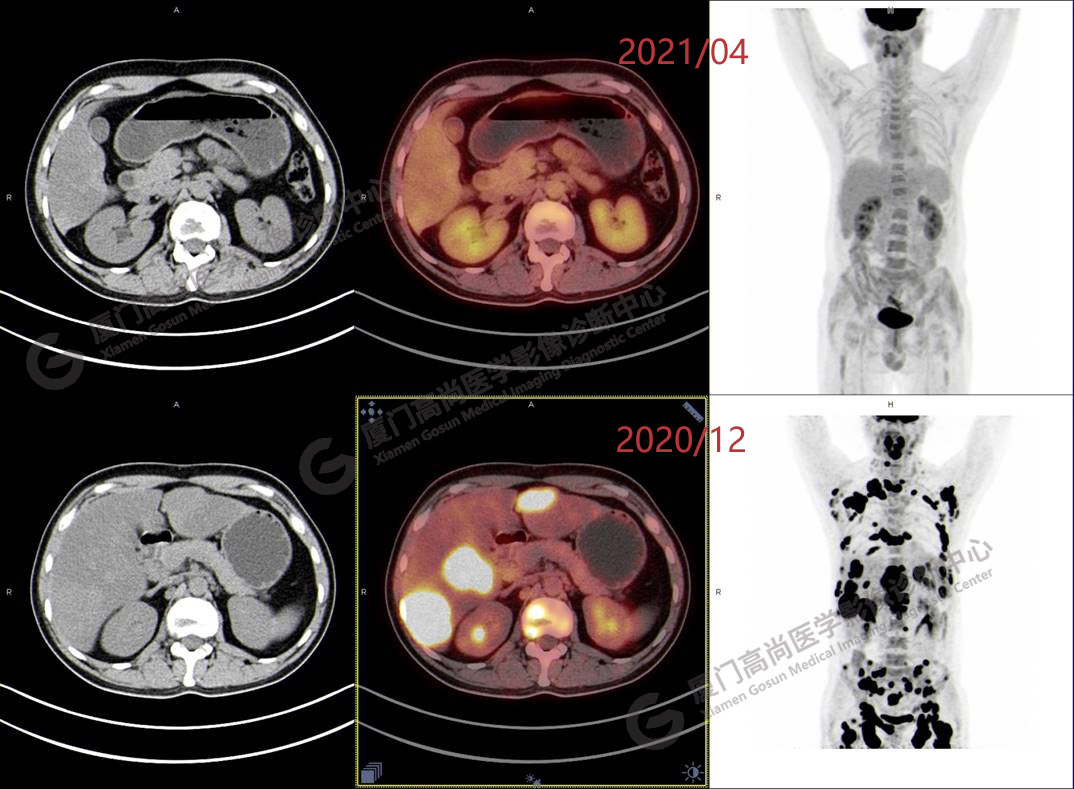

2020.12月本中心PET/CT示:全身多發(fā)腫大淋巴結(jié),代謝不同程度增高;肝臟多發(fā)稍高密度結(jié)節(jié)、脾臟多發(fā)稍低密度結(jié)節(jié),代謝異常增高;全身多發(fā)骨骼溶骨性骨質(zhì)破壞,代謝異常增高,胸2、腰1椎體病理性骨折,診斷為淋巴瘤。隨后,病理確診為彌漫大B細(xì)胞淋巴瘤。

患者化療4個療程后,于2021.04月返我中心復(fù)查,現(xiàn)患者本人已能自主行走,此次更是獨自一人來我中心復(fù)查PET/CT。檢查結(jié)果顯示:原全身多發(fā)病灶基本消失,且病灶代謝基本恢復(fù)正常。以下是患者PET/CT前后對比圖像:

PET/CT前后對比圖像2